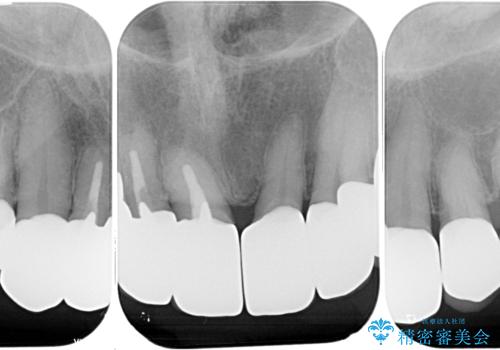

- 前歯のセラミックが欠けたり色調が不揃いであったりすることを気にして来院された患者様です。

20年以上前から、むし歯になったり詰め物が欠けたりする度に部分的に処置を行ってきたそうですが、この際統一感のある前歯にしたいとのことで、上顎前歯9本をオールセラミッククラウンによる補綴治療を行うこととしました。

色調が統一されるだけでなく、歯肉ラインに見えていた茶色の境目も綺麗に改善されました。